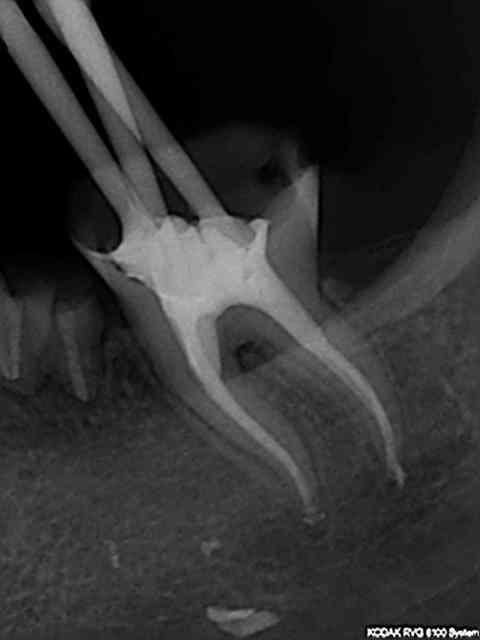

bon j'arrete le r40, une étape en moins

R46 kgfurh - Eugenol

Et dans la foulée comme j'étais en forme.....

R49 ucxpkp - Eugenol